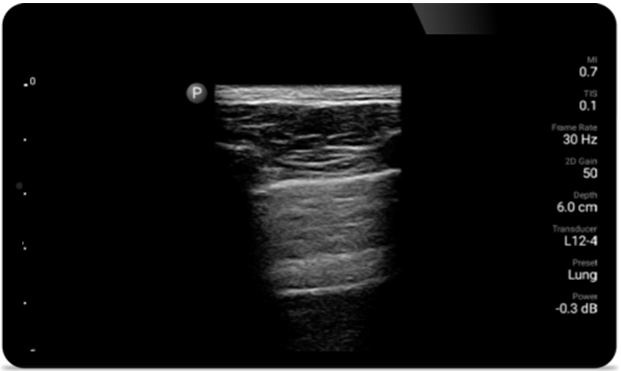

Lumify kann helfen, Patienten schneller zu beurteilen und die Diagnosegenauigkeit häufiger Ursachen von Dyspnoe und anderen Lungenerkrankungen zu erhöhen.